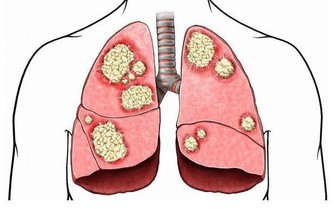

降壓第二招:增加鉀的攝入 在控制鈉鹽攝入的同時,我們還需補充鉀。鉀是人體必須的礦物質,參與細胞內外酸鹼平衡的調節,是維持細胞內滲透壓的主要物質。 鈉鉀攝入的比例,和高血壓、心血管病存在密切關係。如果只限制鈉鹽攝入,不增加鉀的攝入,同樣無法控制高血壓。

鉀:有明顯的降壓作用 富「鉀」飲食是實現「低鈉」的途徑之一。 與鈉的升血壓作用相反,鉀有明顯的降血壓作用,一「份」鉀的降血壓作用可抵消三「份」鈉的升血壓作用。 可能有人會擔心,富「鉀」飲食會不會導致血壓異常降低?這大可放心。 1、只有在攝入高鈉(高鹽膳食)而導致高血壓時,鉀才會發揮降血壓作用; 2、非高鈉膳食導致的高血壓患者不會因補鉀而致使血壓降低; 3、血壓本身就正常的人,攝入鉀也不會使血壓降低。

目前鉀的推薦攝入量是2000毫克/天,若要預防慢性病,推薦量增加到3600毫克/天。 需要特別提醒的是,不要輕易服用含鉀的藥物製劑,因為藥物與食物性質大不相同。 鉀攝入過多同樣不利於心臟健康,反而可能引起心臟傳導阻滯、心跳減慢,嚴重者可導致心跳停止。需要吃藥物鉀的,需聽從醫生指導。